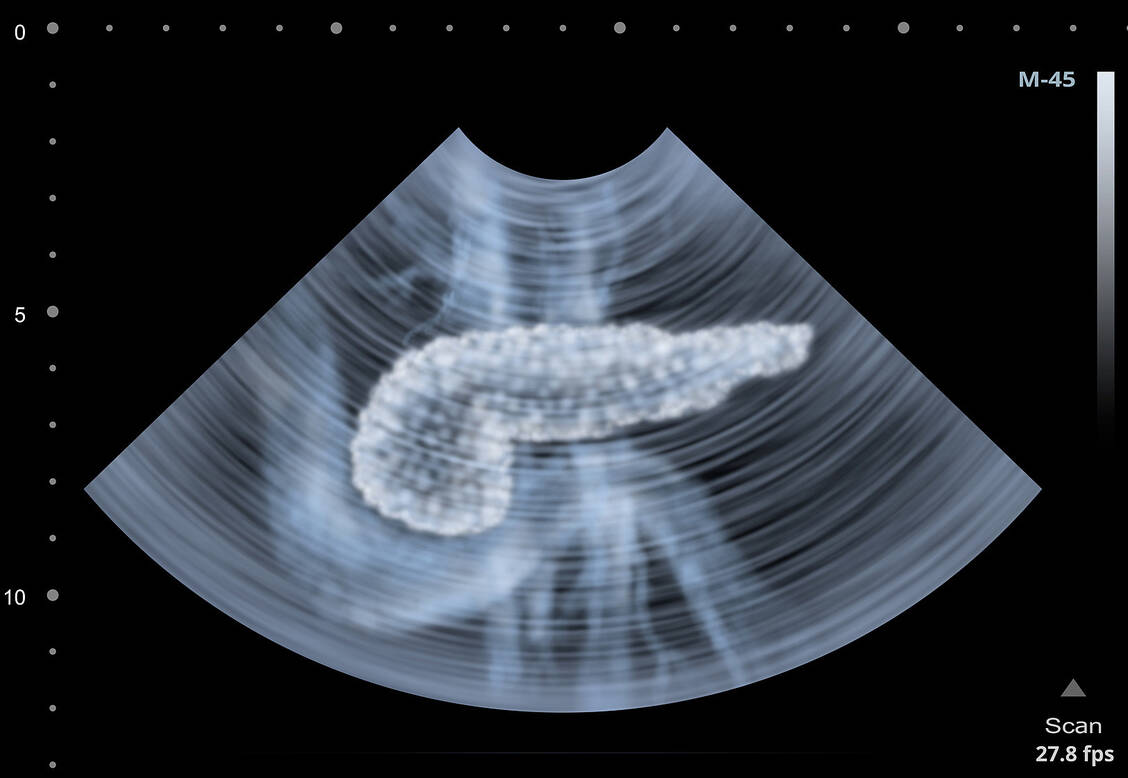

Pankreaskrebs

Zielgerichtete Therapie schenkt ein Jahr Lebenszeit

Pankreaskarzinome haben meist keine gute Prognose. Eine Medikamentenauswahl auf Basis genetischer Testung kann, falls entsprechende Mutationen vorliegen, das Gesamtüberleben im Schnitt um ein Jahr verlängern, zeigt eine neue Studie.

Aufgrund der unspezifischen Symptome im Frühstadium und dem schnellen Fortschreiten der Erkrankung wird das Pankreaskarzinom meist erst in späteren Stadien diagnostiziert und geht mit einer sehr hohen Mortalität einher. Das 5-Jahresüberleben beträgt hierzulande konstant nur rund 10 Prozent, während es bei anderen Krebserkrankungen wie dem Kolonkarzinom seit Jahren rückläufig ist. Dies zeigt die Dringlichkeit zur Entwicklung neuer Therapiestrategien. In einer jüngst in der Fachzeitschrift »Lancet Oncology« publizierten Studie haben Forscher vom Anderson Cancer Centre der Universität Texas untersucht, ob ein patientenindividueller Therapieansatz das Gesamtüberleben steigern kann.

Das Pankreaskarzinom zählt in Deutschland zu den zehn häufigsten Tumorarten mit einer jährlichen Neuerkrankungsrate von rund 17.000. Neben genetischen Ursachen und der chronischen Pankreatitis sind als Risikofaktoren Alter, Rauchen, Adipositas, Alkoholkonsum und Diabetes mellitus bekannt.